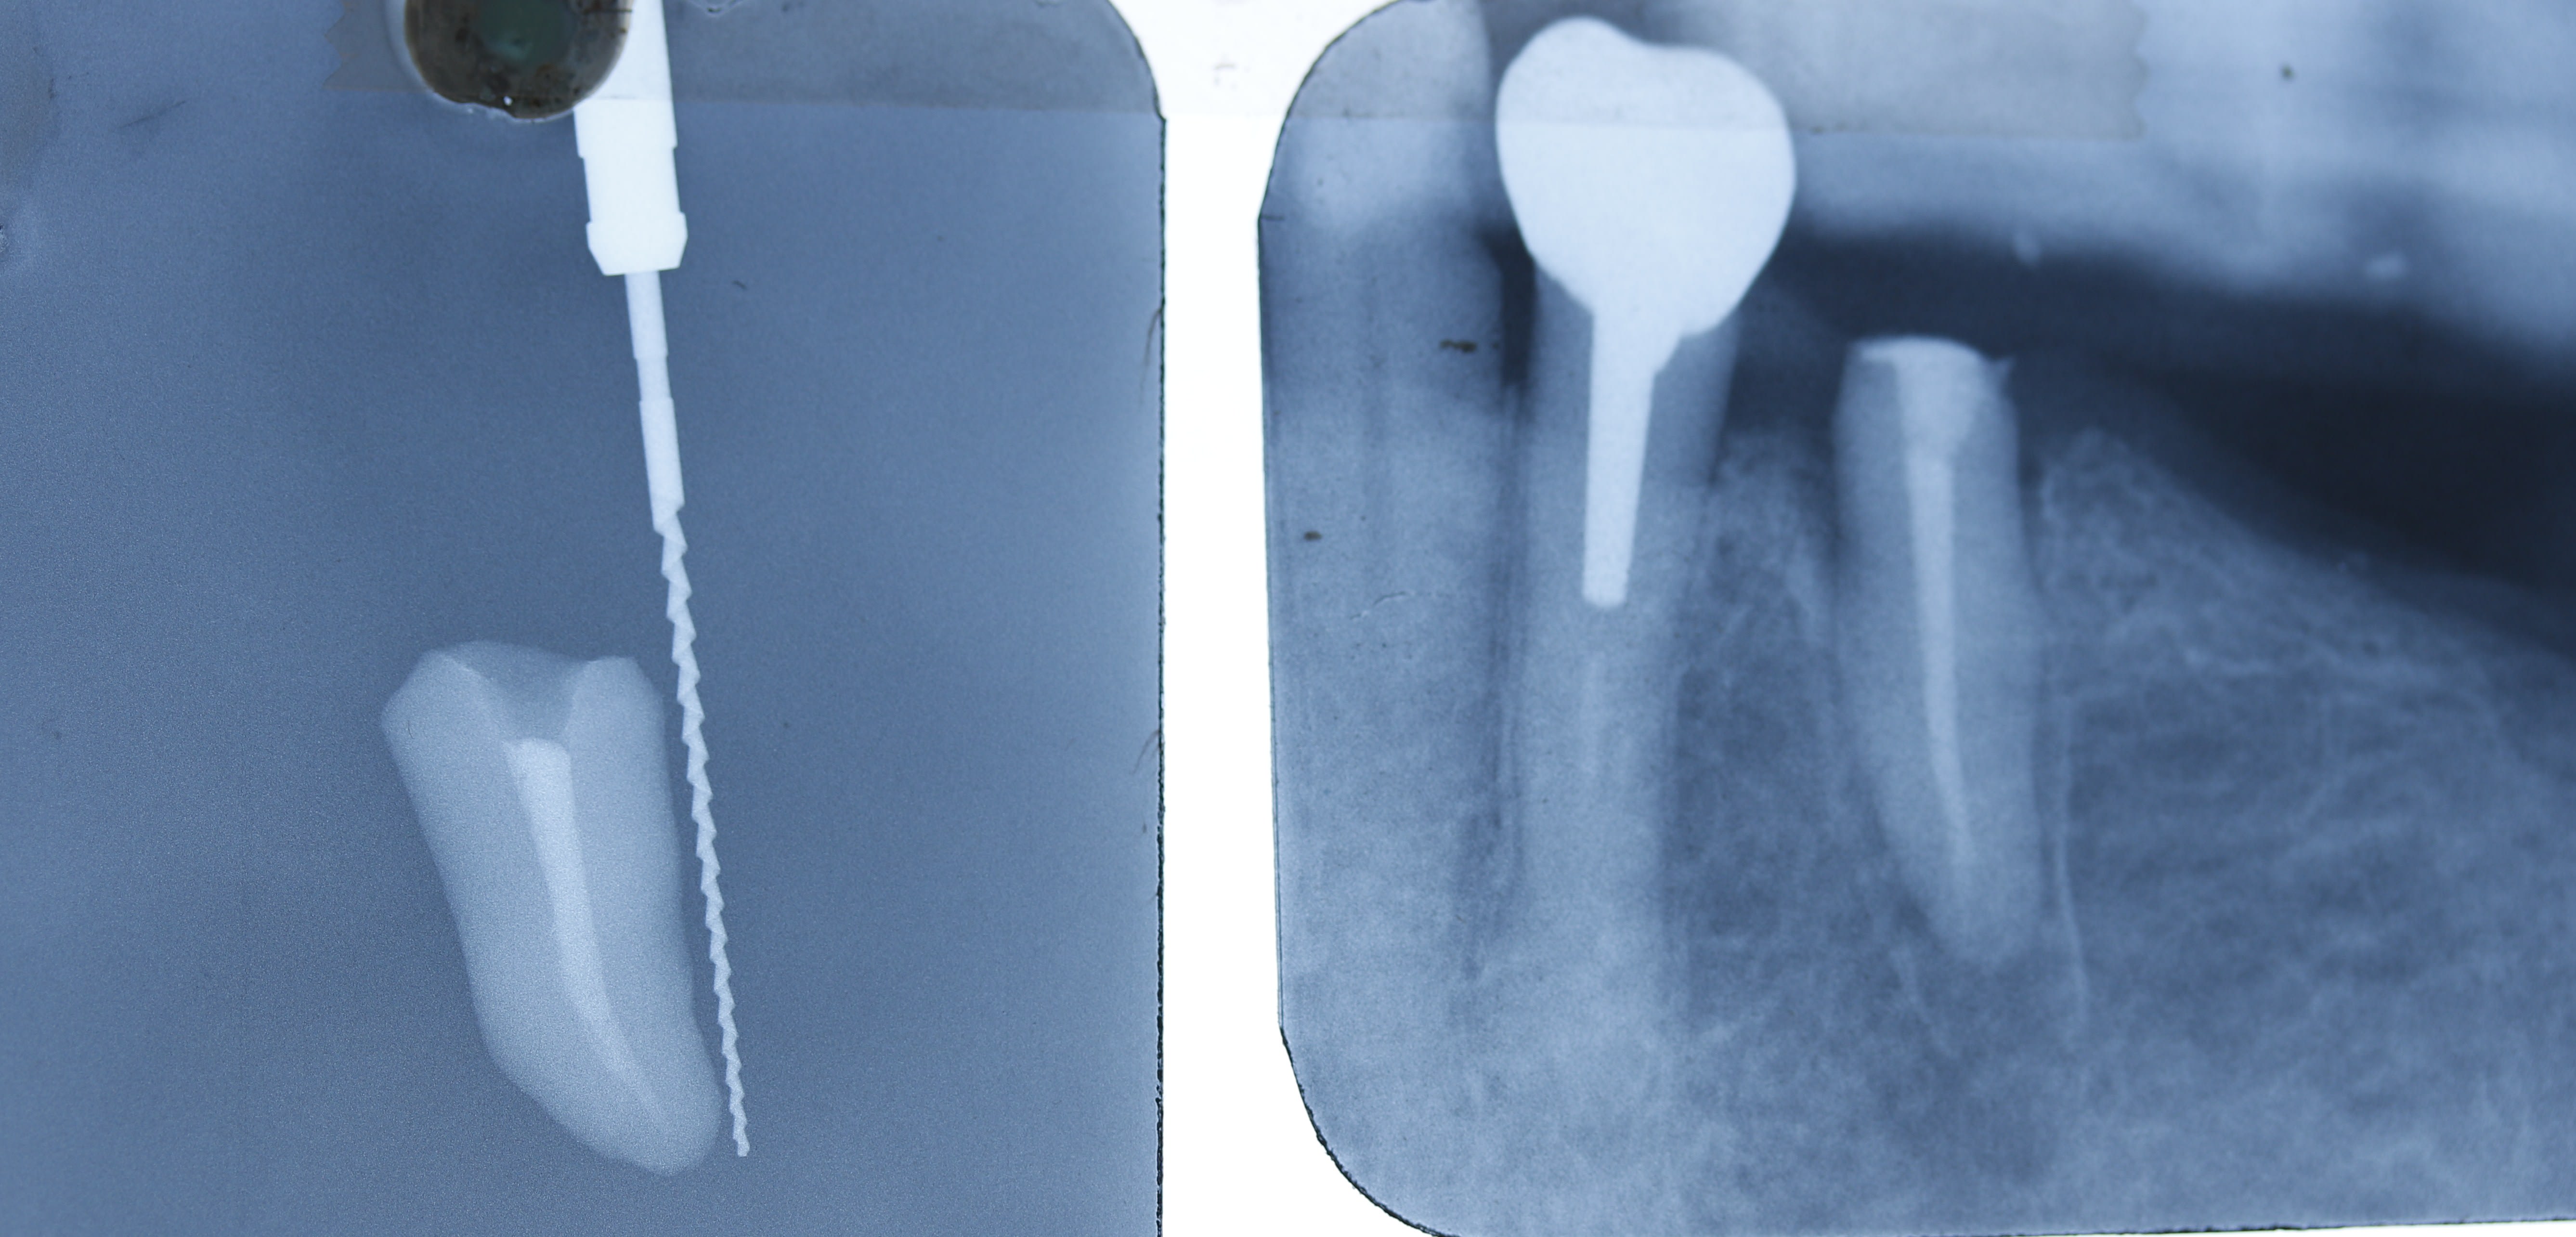

radio de controle de la pm qui avait prermis faire à la fois : - une elongation coronnaire ( de la dent et non par perte d'os bien sur )

- et un rajout d'os par fabrication naturelle d'os pres du nerf dentaire inf .

ç est la 1ere fois que l'on envisage de rajouter de l'os par le bas et non pas par le haut . ouais quand meme :-))))

bref finalement ,cette dent unitaire supporte un crochet de stellite depuis .je vous rappelle que ç est une 35 edentation terminale .

Eri zxwa2f - Eugenol

mg 0896 bimvru - Eugenol

Il doit y avoir un putain de tenon dans la pitchounette, et pas trop le choix non plus.